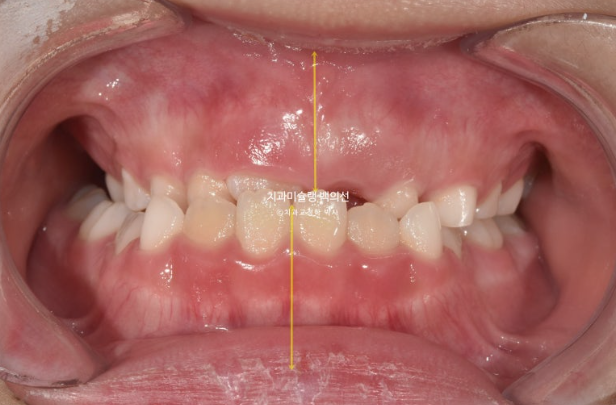

아래앞니와 함께 아래턱이 우측으로 돌아가 있습니다.

두달 후 중심선은 잘 맞아졌습니다.

중심선은 잘 맞으며

비대칭은 개선되었으며 중심선은 맞아졌습니다.

앞니 교합은 좋습니다.